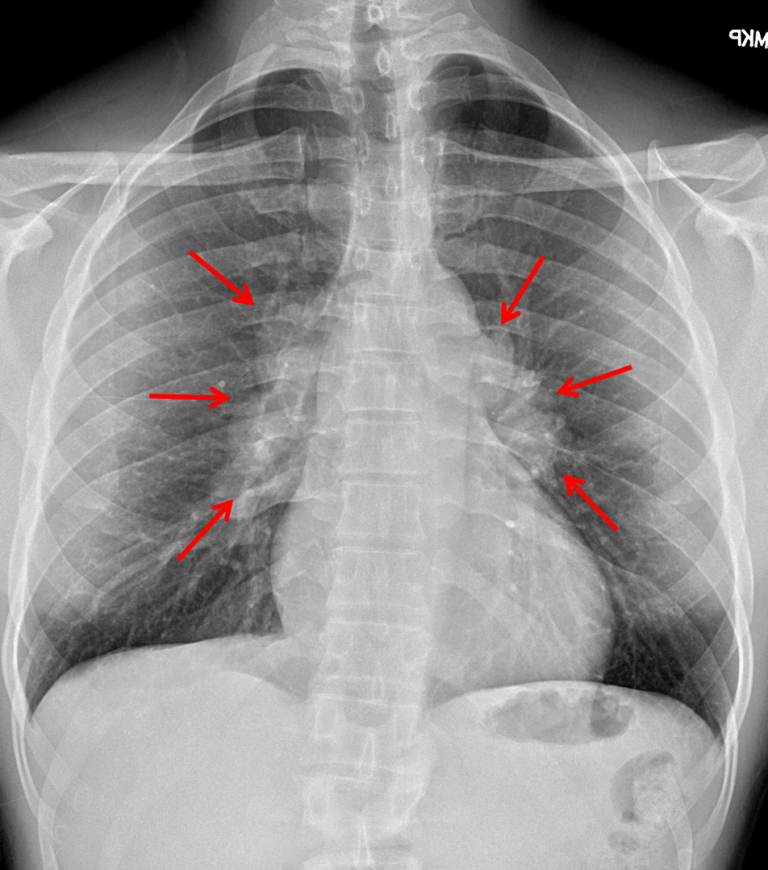

Age: 43

Sex: Male

Indication: Chest pain

Sample ReportBilateral hilar soft tissue prominence is suspicious for lymphadenopathy which could relate to neoplastic disease or systemic granulomatous disease such as sarcoidosis. Consider chest CT for further evaluation.

Otherwise, no evidence of acute cardiopulmonary disease.